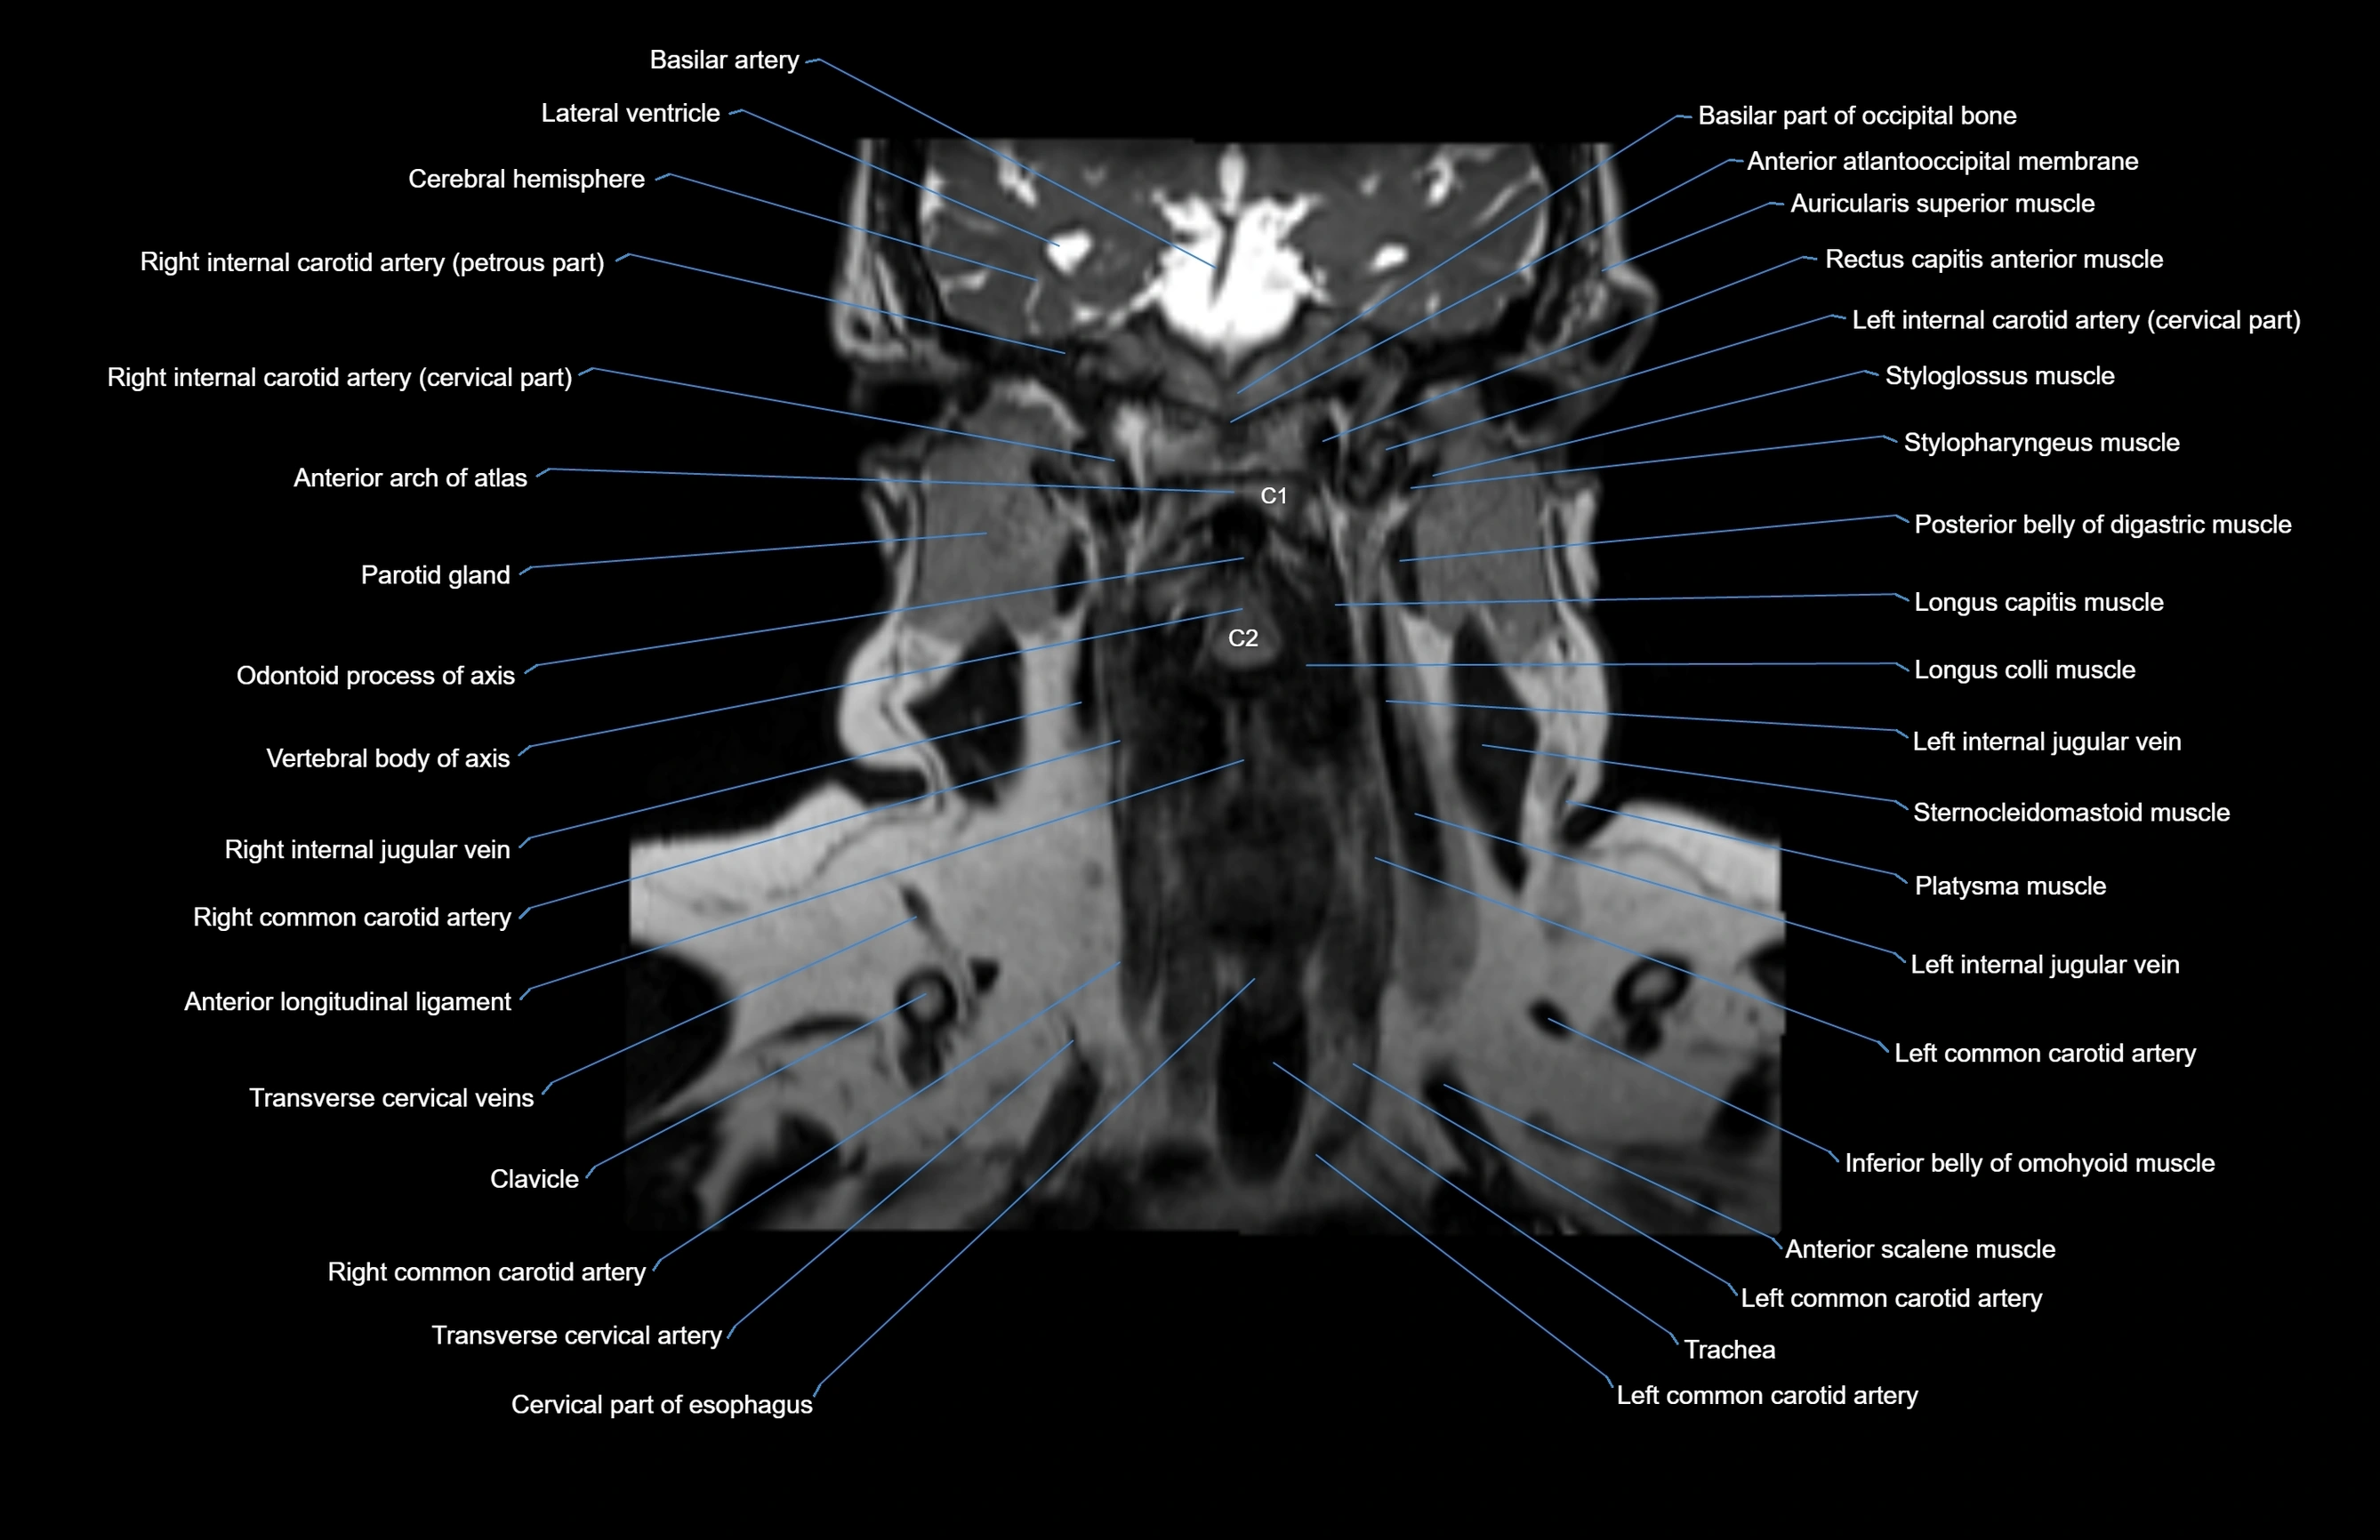

- Anterior arch of atlas

- Anterior atlanto-occipital membrane

- Anterior longitudinal ligament

- Common carotid artery

- Inferior belly of omohyoid muscle

- Internal carotid artery (cervical part)

- Internal carotid artery (petrous part)

- Left common carotid artery

- Longus capitis muscle

- Longus colli muscle

- Occipital bone

- Platysma muscle

- Sternocleidomastoid muscle

- Transverse cervical artery